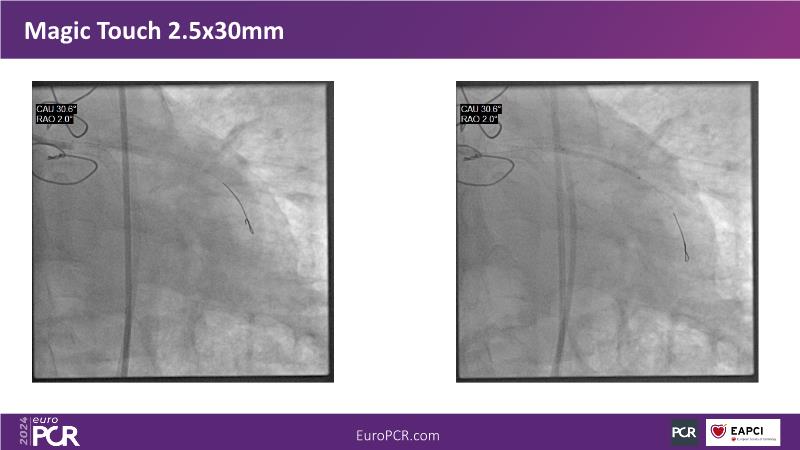

Sirolimus-coated balloon: expanding the scope of indications for complex coronary artery disease treatment

Watch this session to gain case-based insights on using DCBs in complex settings. Learn valuable tips and tricks for optimal DCB application, including the best timing and situations for their use. Discover how to effectively implement a hybrid strategy that combines DES and DCB when needed.

- To get a case based experience on how to use a DCB in complex settings